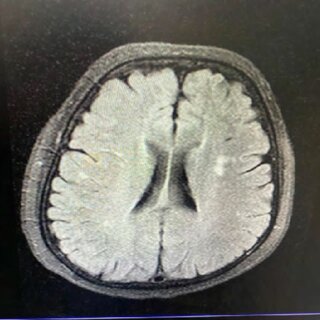

Aurora Lassaletta, psicóloga clínica y afectada de daño cerebral, sufrió un traumatismo craneoencefálico tras un accidente de tráfico en 2005. Desde entonces se ha dedicado a explicar y profundizar en el daño cerebral que no se ve a simple vista, y que en muchas ocasiones es igual o más limitante que otras secuelas visibles.

Haciendo visible lo invisible: el daño cerebral adquirido en primera persona